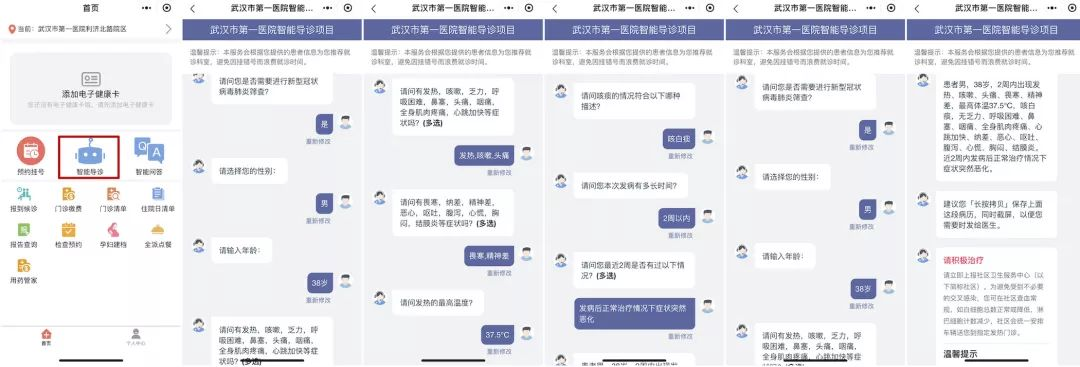

此外,一直专注于AI人工智能医疗的左手医生也针对此次疫情快速推出了 “肺炎筛查”、“预问诊”和“居家隔离指导”三项功能。

据了解,这三款产品都是在左手医生原有AI产品上的升级。例如,肺炎筛查是在左手医生智能导诊和自诊的基础上升级的产品。

在患者端,当用户出现发热、咳嗽、乏力、腹泻等疑似症状时,可登陆左手医生小程序,使用肺炎筛查进行判断。它会模拟医生问诊过程,最后给出相关结论以及诊疗建议和居家指导。

登陆左手医生小程序,可使用肺炎筛查进行初步自我筛查

另外,这款产品还结合医院需求,迅速升级为医院版,作为医生线上接诊患者的前置模块,大大减轻了人力,快速提升了医生效率。

目前,国内有80多家医院包括华中科技大学同济医学院、武汉市中心医院、武汉市第一医院、宜昌市中心人民医院、南京鼓楼医院、贵州医科大学附属医院、成都市第三人民医院等微信公众号或小程序都上线了左手医生这款“肺炎筛查”功能。

在预问诊上,左手医生则是修改、补充了医院发热门诊科室的问诊逻辑,围绕是否是新冠状肺炎、严重程度等对患者展开询问,帮助医生提前采集患者病情,在特殊时期提升医院端端接诊效率。

武汉市中心医院小程序上线了左手医生“肺炎筛查”功能

左手医生CEO张超告诉猎云网,此次疫情中,系统发现了大量疑似人员需要居家隔离,对于这一情况,左手医生面向医院端的产品中还升级了“专病管理”——在原本由AI助理辅助医生完成智能随访、患者自我管理的基础上,针对新冠状肺炎为大众提供14天的隔离指导。

隔离时期内,AI助理会采集患者信息,包括病情、体温、身体状况等信息,一方面上报给管理人员;另外,基于肺炎筛查功能分析居家隔离者的病情并给出相应的指导方案。居家人员也可以通过这个产品自行获得相关知识,并联系管理医生获得相应的服务。

智能导诊帮助医生提前采集患者病情,提升医院端端接诊效率

“我们5号刚刚完成一个新场景的上线,就是利用AI技术帮助社区人员进行疫情防控工作。我们把新冠肺炎筛查、预问诊、居家隔离指导三个产品整合成一整套方案,面向社区人员进行赋能,帮助社区人员更好地了解所在辖区居民的健康状况,支持他们网格化、地毯式管理。”张超表示。